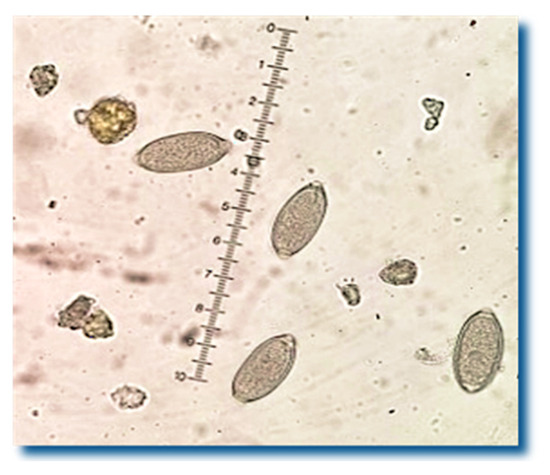

This Special Issue of Pathogens aims to collect current information on parasitic helminths and control strategies in animals and humans. Helminthosis represents a global problem that is commonly addressed under the umbrella of neglected tropical diseases and has not only been attributed to financial losses, but also to losses caused by damage to animal and human health. This is very important under the concept of “One Health” and the relationship with the zoonotic aspects that involve the various diseases caused by helminths. The collection of data is necessary with the use of biotechnological or customary tools to establish the updated prevalence, which is important to determine the reality of each location and can indicate whether the control measures adopted are effective or even whether the unprecedented reports may indicate the growth of one of these agents.

Pathological mechanisms and lesions caused by these agents can also indicate the various damages related to them. Among the advances for the control strategies of helminthosis are biological control, vaccines, resistant breeds, nanotechnology, chemicals, and even new phytotherapeutic anthelmintics. This Special Issue aims to present the parasitic helminths and control strategies in animals and humans. We, therefore, invite our colleagues to send in their work so that we can fulfil this objective.